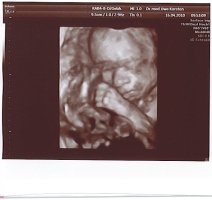

Tolle Fotos hier übrigens. Stelle mal ein paar neue von unserer Kleinen rein. Am Freitag hat sie sich das erste Mal bequemt, ihr Gesicht zu zeigen. Ich war echt fasziniert. Es ist so schön, dass Baby zu sehen. Bin jetzt schon total verliebt. Was soll das erst werden, wenn sie da ist?! 😛feif

• 8.jpg

8.jpg

82,3 KB · Aufrufe: 426

• 9.jpg

9.jpg

78,3 KB · Aufrufe: 424

• 10.jpg

10.jpg

85,3 KB · Aufrufe: 428